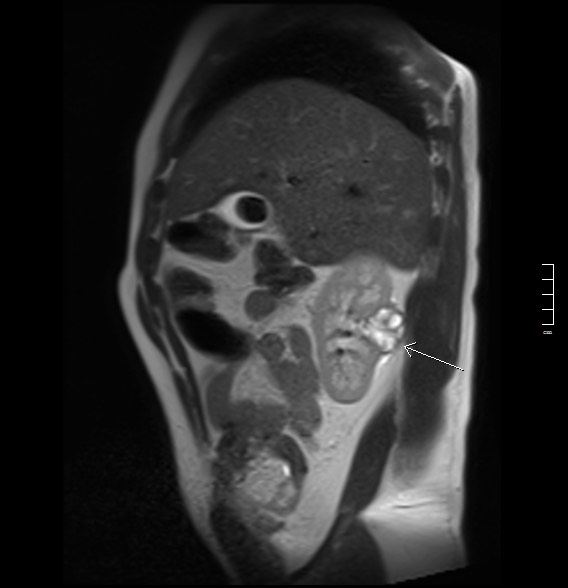

2913. Указанное стрелкой кистозно-солидное образование локализуется в _____ сегменте почки